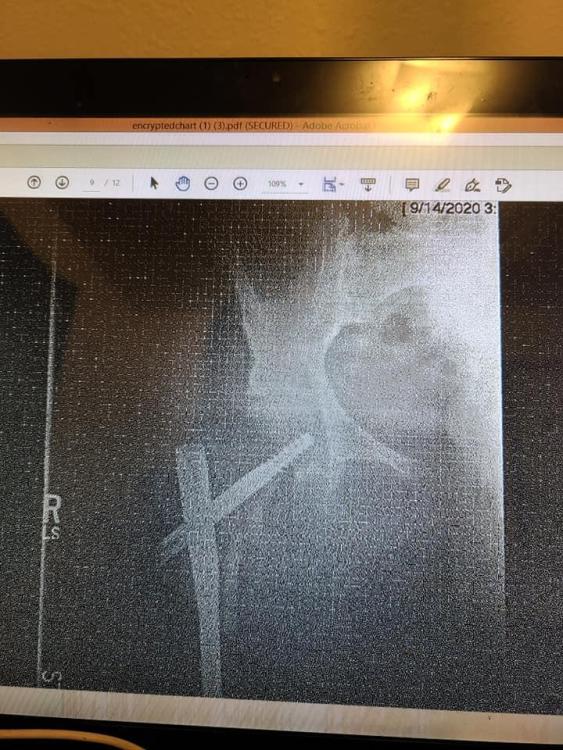

I know what you mean.    In August of 2020,  I slipped while bringing my dog back into my apartment.  I did the splits and shattered my greater trochanter in my right leg. Let's just say that I'm filled with titanium, nails and screws in my right leg.    I'm still not 100% but I can walk now.     It was a rough few months.

121552598_3566939606691023_4773675554572697356_n.jpg